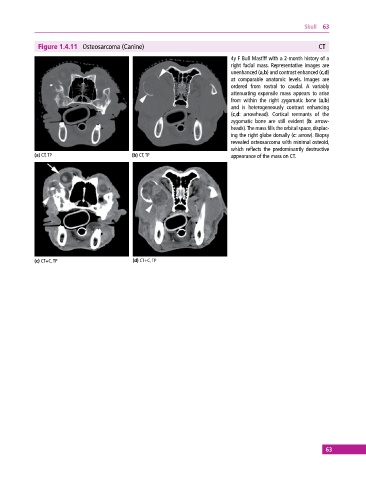

Figure 1.4.11 Osteosarcoma (Canine) CT

4y F Bull Mastiff with a 2‐month history of a

right facial mass. Representative images are

unenhanced (a,b) and contrast enhanced (c,d)

at comparable anatomic levels. Images are

ordered from rostral to caudal. A variably

attenuating expansile mass appears to arise

from within the right zygomatic bone (a,b)

and is heterogeneously contrast enhancing

(c,d: arrowhead). Cortical remnants of the

zygomatic bone are still evident (b: arrow-

heads). The mass fills the orbital space, displac-

ing the right globe dorsally (c: arrow). Biopsy

revealed osteosarcoma with minimal osteoid,

which reflects the predominantly destructive

(a) CT, TP (b) CT, TP appearance of the mass on CT.